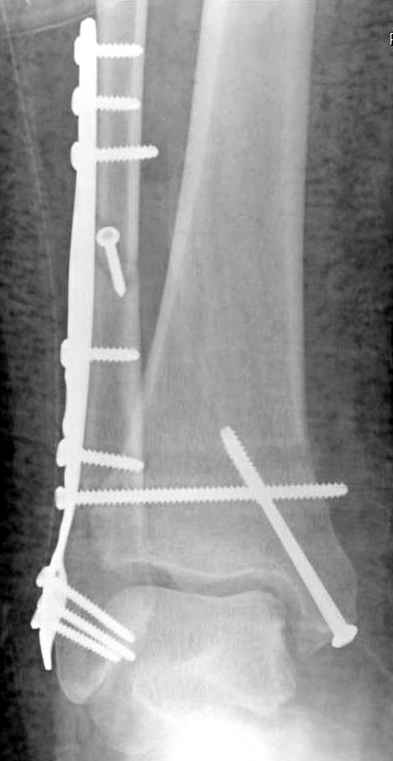

Операция 29 июля

Риторический вопрос - в каком руководстве рекомендован такой способ остеосинтеза наружной лодыжки?

Очевидно, такой результат операции был запрограммирован. При невосстановленной длине и практически нефиксированной малоберцовой кости (этот кортикальный винт - как карандаш в стакане), при неустраненном подвывихе, невправленной и тоже нефиксированной внутренней лодыжке нет стабильной вилки сустава. Если такую операцию сделать даже сразу, а не через 4 месяца, то результат ожидаем

тот же.

Ну а уж если выбран остеосинтез - нначать надо было с репозиции малоберцовой кости с точным восстановлением длины, с фиксацией треть-трубчатой пластиной по задней поверхности. Позиционный винт

избыточен - повреждение практически подсиндесмозное. А если бы

действительно было повреждение синдесмоза - в 4 месяца позиционный винт - не решение. Внутренню лодыжку такую - надо было бы спицами и проволочной петлей. Извините за эти банальности.

Если до сих ничего не сделано, с артродезом сустава в данный момент я бы повременил, на выставленных январских снимках хорошо сохранившийся сустав, а в "мортиз" (трехчетвертной) и на боковых снимках не менее 5 мм укорочение малоберцовой кости. Косые переломы лучше фиксировать пластинами, как то мы разбирали случай, где было отмечено, что это закон "таранная кость всегда следует за малоберцовой".

В данном случаи я бы уговорил больного на реконструкцию, для этого после удаления шурупов, спереди очистить от рубцов синдесмоз, несросшуюся наружную лодыжку - остеотомия по линии перелома и компрессирующий (lagging technique) кортикальный шуруп 3.5 мм по поперечнику остеотомии. Следующий этап - восстановление длины малоберцовой за счет удлинения, сделать поперечную остеотомию где-то на уровне сантиметр выше вашего синдесмозного шурупа, наложить длинную пластинку, прикрепить пластину за дистальный конец двумя или тремя шурупами; сохраняя контакт пластины с костью, имеющимся

compression&tension device AO system (при отсутствии любой lamina spreader подойдет, создать дистанцию между пластиной и шурупом, проведенным проксимальнее пластины) толкая проксимальный отдел пластины, низвести пластину, мортиз рентгенограмма подскажет на сколько. Если заранее сделать предоперационный план (ренгенограмма другой стороны), тогда точно можно определить, на сколько вам необходимо сделать поперечную остеотомию малоберцовой кости, для закрытия создавшегося дефекта.

Убедившись, что желаемая длина восстановлена, окончательная фиксация пластины, при этом через пластину пару 3.5 мм шурупов на синдесмоз, предпочтительно в четыре кортекса и оставить на 3 мм длиннее, если под нагрузкой синдесмотический шуруп сломается, сломанный конец легче удалить с медиальной стороны.